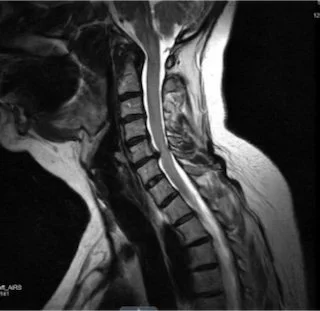

MRI scan of a human spine showing vertebrae and spinal cord.

Anterior Cervical Discectomy and Fusion (ACDF) is a procedure performed through the front of the neck to treat nerve or spinal cord compression in the cervical spine.

Approaching the spine from the front allows the surgeon to directly access the disc and relieve pressure on the nerves or spinal cord.